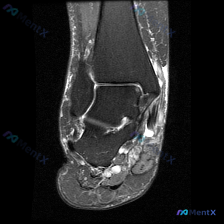

本次提供的是单张膝关节矢状位T1加权MRI,核心问题是:临床关注「软骨异常」,但影像初步观察未见明确异常。

- 图像质量合格,定位为膝关节正中矢状位,可观察后交叉韧带、半月板体部

- 股骨远端、胫骨近端骨皮质连续,骨髓信号无异常,关节对位良好

- 股骨髁、胫骨平台关节软骨形态完整,表面未见明确局灶缺损或不规则改变

- 半月板前后角形态信号正常,无撕裂征象;后交叉韧带形态连续走行正常

- 关节腔内无明显积液,髌下脂肪垫、腘窝未见异常占位

- 总体结论:本张图像未见明确结构性损伤